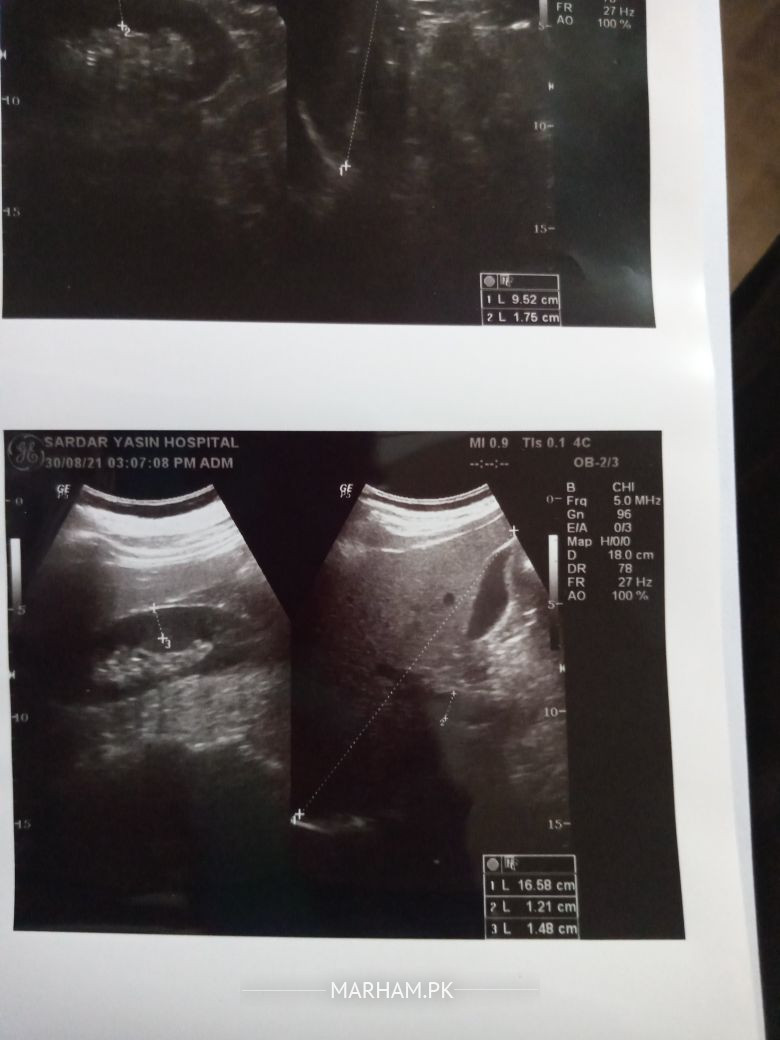

no nothing serious but your disease must not progress further.its good that all results are normal.yes NASH is detected in ultraouns and extent of NASH Is detected by fibroscan.within 2 months your ultrasound will come clear insha Allah